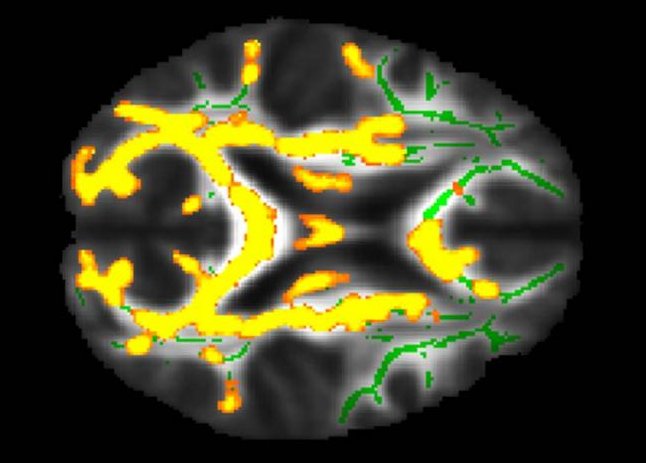

Per tentare di individuare presto il rischio di MA, dei ricercatori hanno valutato l'associazione tra scansioni MRI del cervello e assorbimento di amiloide e tau sulle scansioni PET, con l'indice di massa corporea (IMC), obesità, resistenza all'insulina e tessuto adiposo addominale (grasso) in una popolazione di mezza età cognitivamente normale. Si ritiene che le proteine amiloide e tau interferiscano con la comunicazione tra le cellule cerebrali.

La risonanza magnetica cerebrale ha misurato lo spessore corticale delle regioni cerebrali che sono colpite dal MA. La PET è servita per esaminare la patologia della malattia in un sottoinsieme di 32 partecipanti, concentrandosi su placche amiloidi e grovigli tau che si accumulano nel MA.

I ricercatori hanno scoperto che un rapporto grasso viscerale-sottocutaneo più elevato era associato a un maggiore assorbimento del tracciante PET amiloide nel precuneo, la regione nota per essere influenzata presto dalla patologia amiloide del MA. Questa relazione era peggiore negli uomini che nelle donne. I ricercatori hanno anche scoperto che valori più elevati di grasso viscerale erano correlati ad un aumento del carico di infiammazione nel cervello.